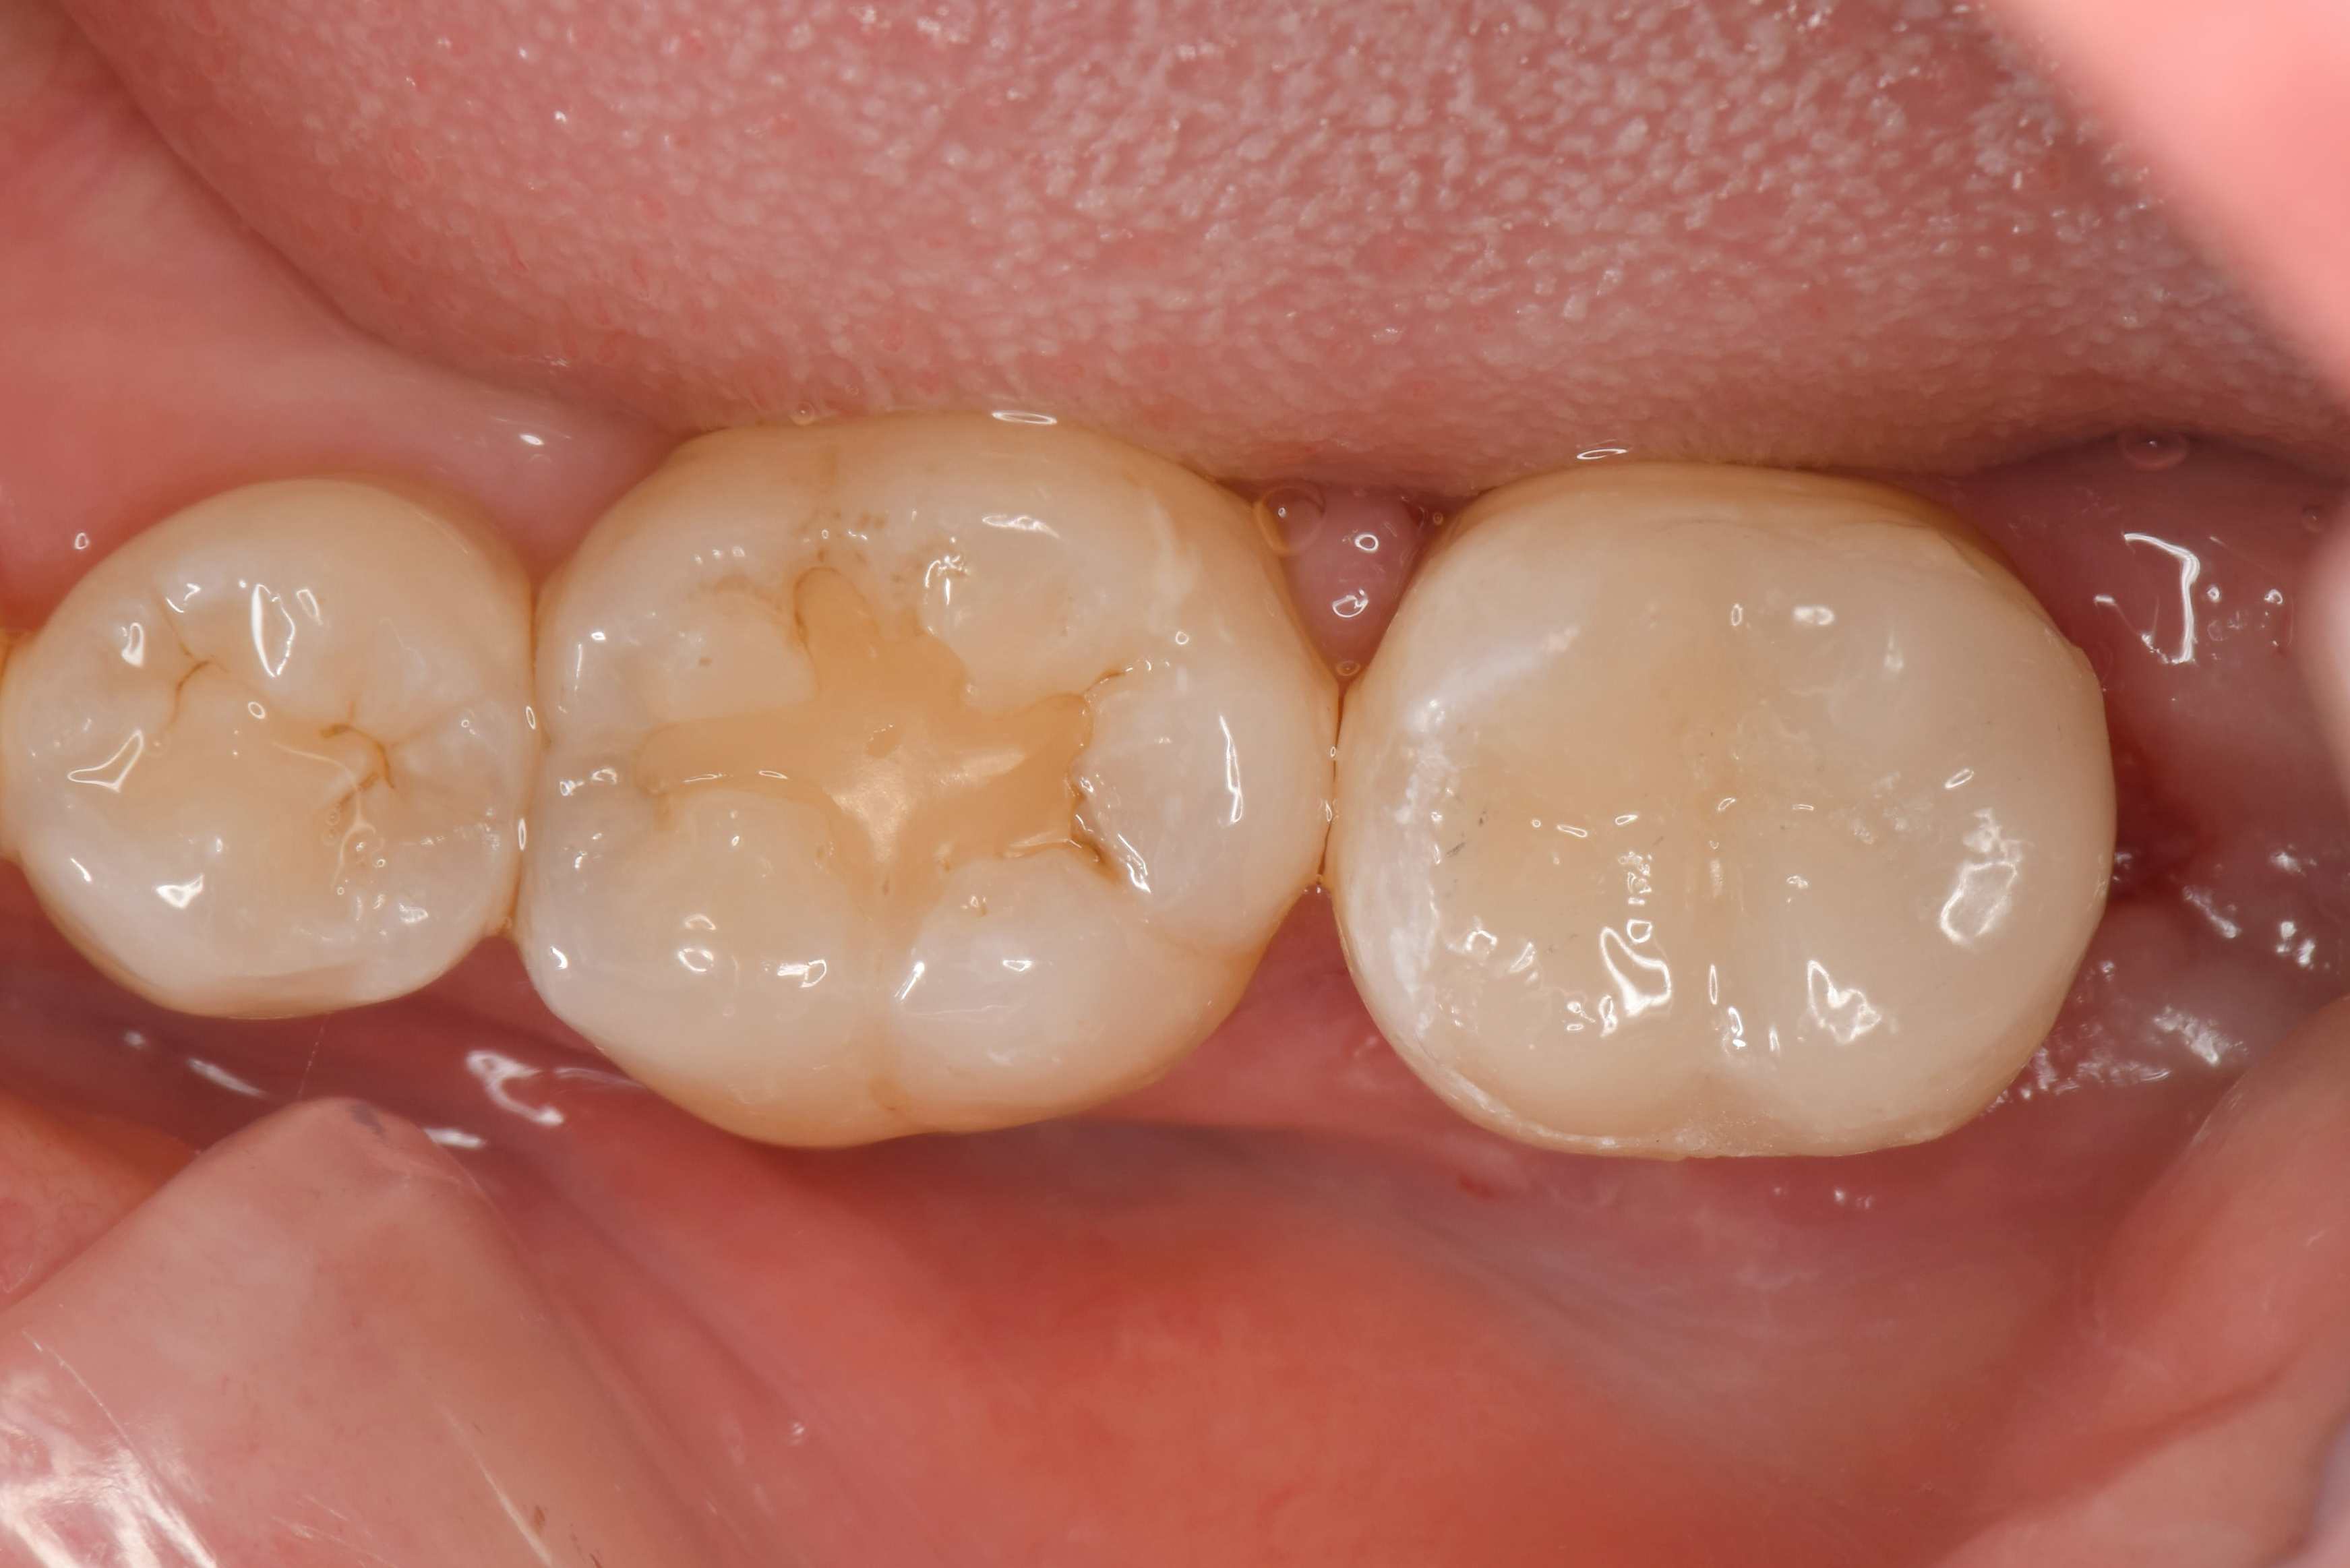

形成後の写真です。これから型取りをする所ですが、歯が半分以上残っていることがお分かりいただけると思います。

オーバーレイ(テーブルトップベニヤ)は、通常のセラミックの被せ物と比べ歯を削る量が圧倒的に少ないため、歯が痛む確率を下げることができます。